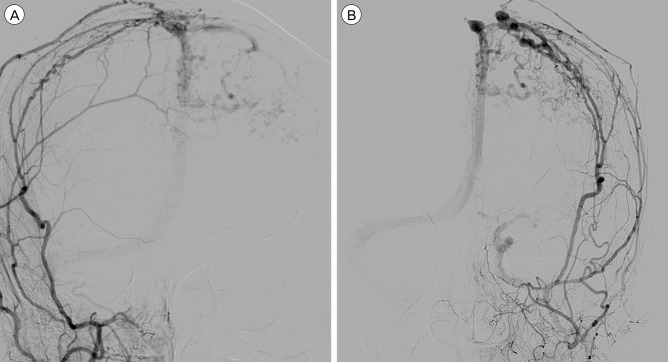

我们报告了一例硬脑膜动静脉瘘(DAVF)病例,在四个月的随访期间,患者的静脉引流模式自发地从 Borden II 型转变为 III 型。入院时,患者的神经系统状况恶化,并出现新的癫痫发作。入院后,使用 Onyx® 通过脑膜中动脉进行了血管内栓塞治疗。血管造影证实硬脑膜动静脉分流完全阻塞,患者的临床症状有所改善。虽然大多数硬脑膜动静脉瘘病例的临床过程和转归模式都是良性的,但仍需密切随访,以发现潜在的恶化。

We report a case of dural arteriovenous fistula (DAVF) that showed spontaneous conversion of venous drainage pattern from Borden type II to type III within a four month period of follow-up. Upon admission, the patient presented with aggravated neurologic status and newly developed seizure. After admission, endovascular embolization was performed through the middle meningeal artery with Onyx®. Complete obliteration of dural arteriovenous shunt was confirmed by angiography, and the patient's clinical symptoms improved. Although most cases of DAVF show benign clinical course and conversion pattern, close follow-up is required to detect potential aggravation.